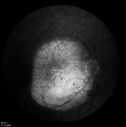

Choroidal Metastases - Both Eyes - Exudative Retinal Detachmentvu 1412 fois58-year-old man smoke a pack of cigarettes a day. He has had some ribcage pain for about the last two weeks. He also had a sinus infection for about two weeks, and he has also had hazy vision on the superior visual field in the left eye for about the last two weeks. vision is 20/25 in both eyes

Choroidal Metastases - Both Eyes - Exudative Retinal Detachmentvu 907 fois58-year-old man smoke a pack of cigarettes a day. He has had some ribcage pain for about the last two weeks. He also had a sinus infection for about two weeks, and he has also had hazy vision on the superior visual field in the left eye for about the last two weeks. vision is 20/25 in both eyes

Choroidal Metastases - Both Eyes - Exudative Retinal Detachmentvu 823 fois58-year-old man smoke a pack of cigarettes a day. He has had some ribcage pain for about the last two weeks. He also had a sinus infection for about two weeks, and he has also had hazy vision on the superior visual field in the left eye for about the last two weeks. vision is 20/25 in both eyes

Choroidal Metastases - Both Eyes - Exudative Retinal Detachmentvu 796 fois58-year-old man smoke a pack of cigarettes a day. He has had some ribcage pain for about the last two weeks. He also had a sinus infection for about two weeks, and he has also had hazy vision on the superior visual field in the left eye for about the last two weeks. vision is 20/25 in both eyes